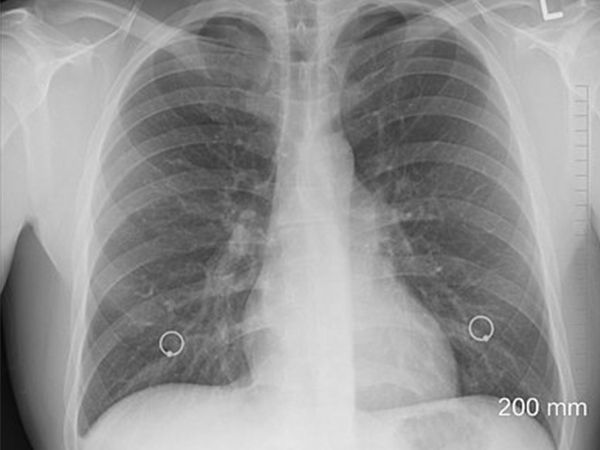

- Chest X-ray: This is done to obtain the images of the lungs.